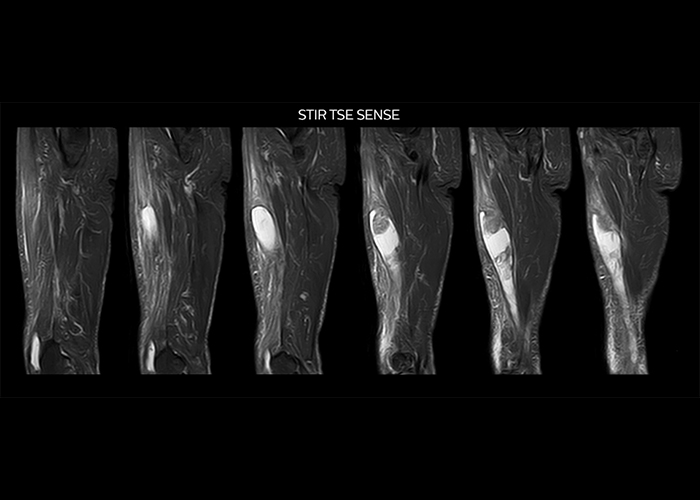

“To avoid coil changes we plan examinations of similar anatomies back to back, such as head and spine. Multiva helps us here a lot because coils don’t need to be changed frequently. Moreover, thanks to parallel imaging technology and 16-channel HeadSpineTorso and 8-channel MSK coils we are able to achieve excellent image quality. In this way Multiva helped us to increase both image quality and productivity.”

“Neurological cases, such as brain and spine imaging, represent the largest share in our MR scanning, followed by musculoskeletal cases. In general, we use simple and basic imaging protocols. But occasionally, we use advanced techniques for problematic cases if necessary.

“Since we have Multiva, we have improved our workflow, because it has been so easy for our operators to learn and use Multiva. Our operators notice that the coils are lightweight and coils don’t need to be changed frequently. The user interface is easy to use. Features like this help us to scan a high number of patients. For instance, the musculoskeletal coils can be used interchangeably, and due to the user-friendly interface, the number of mistakes such as, for example, correct coil element selection has decreased significantly, because the system does it automatically by itself.”